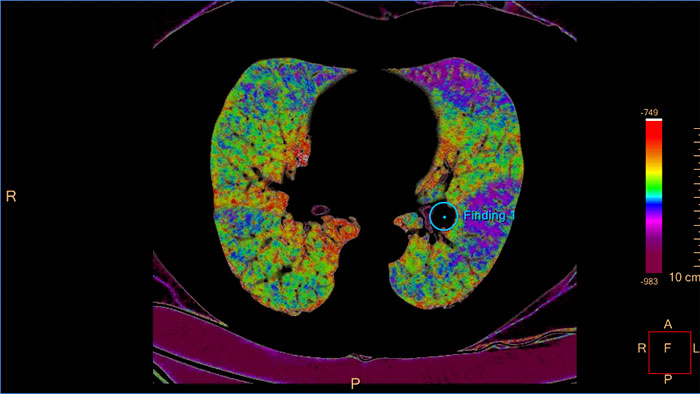

CT COPD to quantify diffuse lung disease

The clinical application helps visualize and quantify the destructive process of diffuse lung disease (e.g. emphysema), providing a guided workflow for airway analysis, reviewing and measuring airway lumen, and assessing air trapped.

COPD

CT COPD

Quantify diffuse lung disease

CT COPD helps visualize and quantify the destructive process of diffuse lung disease (e.g. emphysema). The application provides a guided workflow for airway analysis, reviewing and measuring airway lumen, and assessing air trapped.

Benefits

• Automatic lung and lobes segmentation.

• Automatic airway extraction, airway tree segmentation and navigation path extraction, enabling the measurement of airway parameters such as lumen diameter and wall cross-section.

• Tools for qualitative and quantitative temporal comparison of up to four follow-up studies in order to determine the progression of the disease.